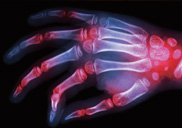

·ù¸¶Æ¼½º°üÀý¿° VS ÅðÇ༺°üÀý¿° ¾î¶»°Ô ´Ù¸¦±î?